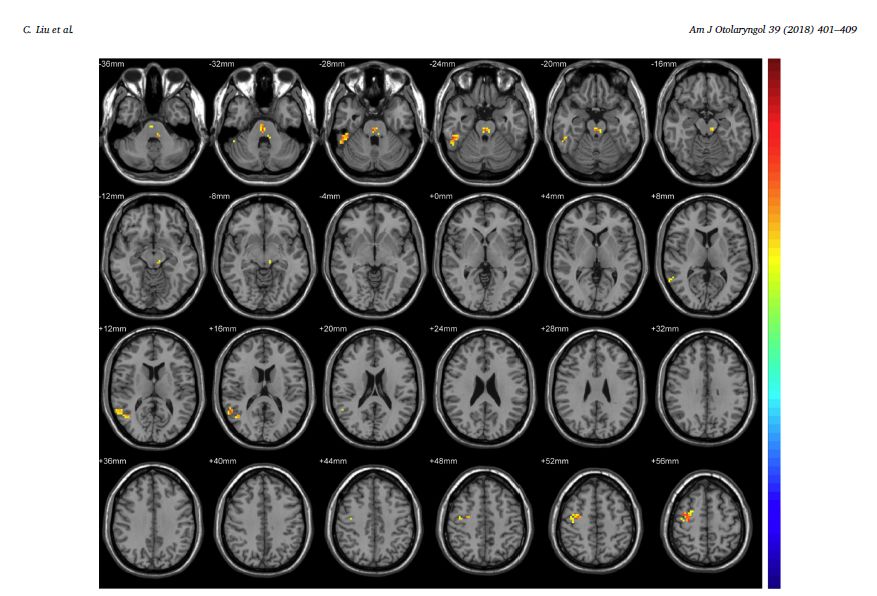

CAABT临床预研究由首都医科大学附属北京友谊医院耳鼻喉科牵头,协英国爱丁堡大学HX医学教育管理研究所等国内外临床研究机构,经过多年研究取得的阶段性成果。特别是采用CAABT法和掩蔽法对照,通过功能性核磁fMRI进行客观判断,得到符合统计学意义的结果,CAABT能够改变脑活动的变化,治疗效果优于对照组掩蔽疗法。

结果:几乎所有患者在三个月的治疗后,耳鸣烦躁度均减轻。耳鸣残疾度量化表与视觉模拟评分表均表明耳鸣严重度降低。rs-fMRI功能性核磁成像结果显示受试者右中额叶脑回和右颞上回的ReHo值显著降低,表明耳鸣程度显著减弱。